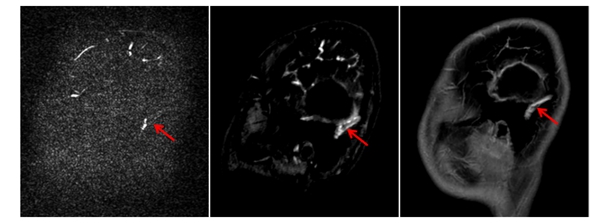

▲对比检查显示,CE-MRV(中间图)较常规PC-MRV(左图)能更准确显示乙状静脉窦内血栓的位置和范围,为临床治疗提供了可靠依据,患儿经过十天对症治疗后复查显示同一部位血栓明显缩小(右图)。

在儿科团队的全程监护下,小卓顺利完成对比增强磁共振静脉成像(CE-MRV)检查。放射影像科团队通过优化扫描方案和动态监测造影剂循环时相,成功获取了高质量的诊断影像,清晰显示了颅内静脉窦血栓的具体位置及累及范围。基于这一精准的影像学评估,儿科治疗团队为小卓制定了个体化综合治疗方案,最终头痛等症状明显改善,后续影像复查证实血栓范围明显缩小,治疗效果达到预期目标。

磁共振检查结果显示,小卓左侧颞叶和顶叶出血,左侧乙状窦、横窦可见高信号灶,提示可能有静脉窦血栓形成,同时合并左耳中耳炎。放射影像科第一时间启动危急值报告机制,科室主任范淼与黄雪琼一同为患儿进行病情分析,并就下一步检查和治疗展开讨论。“患儿脑出血极可能是颅内静脉血栓(CVT)导致血液回流受阻所致,建议进行磁共振头部静脉增强检查(CE-MRV),明确血栓范围。”范淼说道。